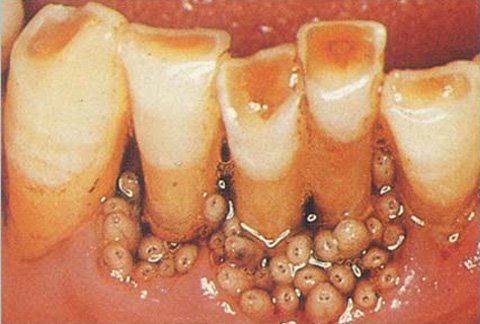

Bé Ana Cardoso, 10 tuổi luôn cảm thấy có gì đó ngọ nguậy trong miệng nên đã nói với mẹ. Khi bé gái há miệng cho mẹ xem thì mẹ bé không nhìn thấy gì cả. Đưa bé đi gặp bác sĩ. Khi đó bác sĩ mới phát hiện ra ổ giòi hơn chục con làm tổ trong nướu của bé.

Ana được chẩn đoán mắc bệnh giòi trong miệng (Myiasis), một tình trạng nhiễm trùng sâu non xảy ra ở cả người và động vật.

Đại diện đội phẫu thuật nha khoa nói: "Có tất cả 15 con giòi trong miệng bệnh nhân. Chúng tôi quay video cảnh gắp chúng ra do đây là một trường hợp khá hiếm gặp. Thông qua video này, chúng tôi cũng muốn cho bố mẹ bé gái xem và cảnh báo với những người khác".